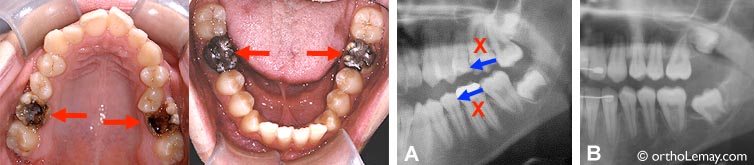

Cas où 4 molaires sévèrement endommagées ont été extraites (flèches rouges et X) pour éviter des travaux dentaires importants (traitements de canal et couronnes). Les espaces de la largeur d’une molaire (±11 mm) ont été fermés (flèches bleues) évitant d’avoir à remplacer les dents extraites. Radiographies : (A) Avant les extractions. (B) Après l’orthodontie, une fois les espaces fermés (côté gauche). Pour voir ce cas une fois traité.